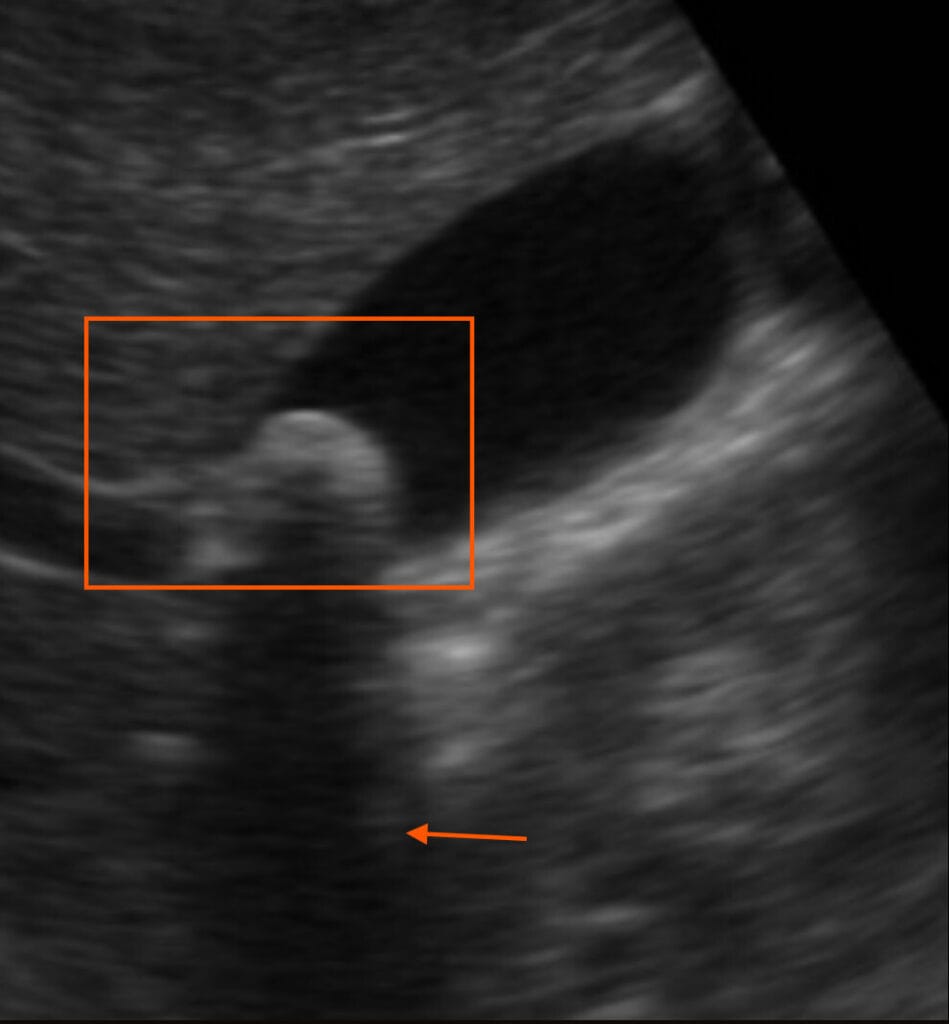

초음파 소견상 특징

- Hyperechoic stone

- Posterior Acoustic Shadowing